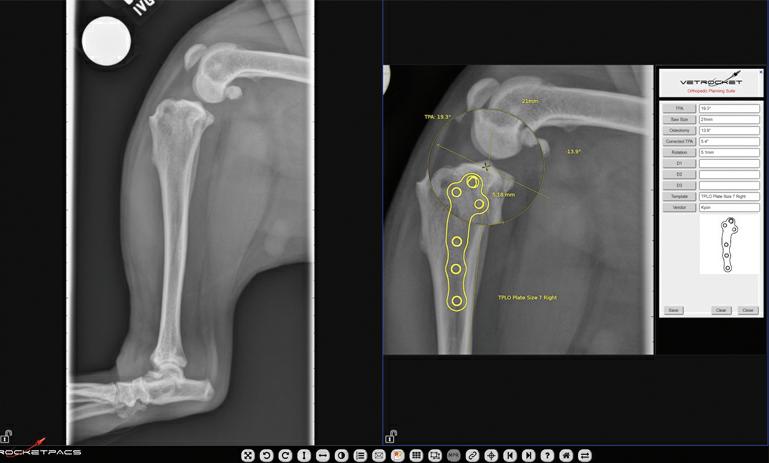

Interventional Radiology at Animal Referral Hospital (ARH) Homebush

ARH Homebush’s Internal Medicine Specialist, Dr Tim Hugo BVSc (Hons 1) FANZCVS (Small Animal Medicine) recently undertook specialised training in cardiac interventional radiology procedures in the USA led by renowned professor of cardiology at Colorado State University Dr. Brian Scansen. Focused on treating common congenital heart diseases such as patent ductus arteriosus and pulmonic stenosis, the training emphasised catheter-based treatments. Interventional Radiology offers new possibilities for conditions previously treated with open surgery, resulting in reduced patient morbidity and shorter hospital stays. ARH Homebush provides various interventional radiology treatments, including stenting and coiling for intrahepatic portosystemic shunts.